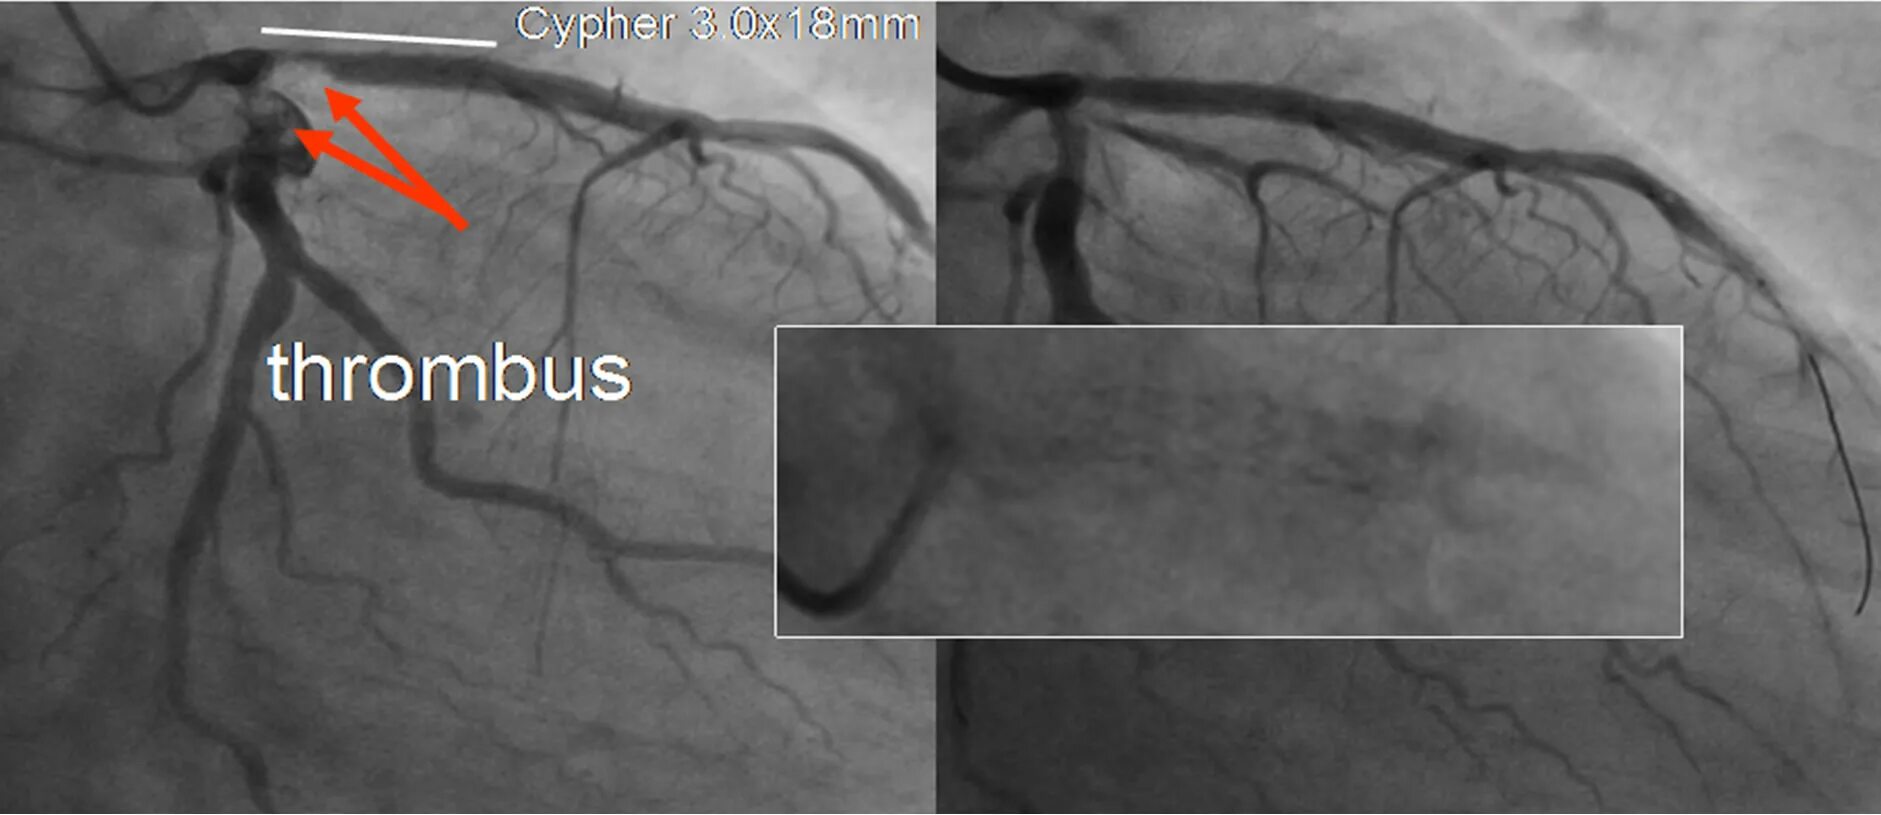

Атеросклероз левой коронарной артерии